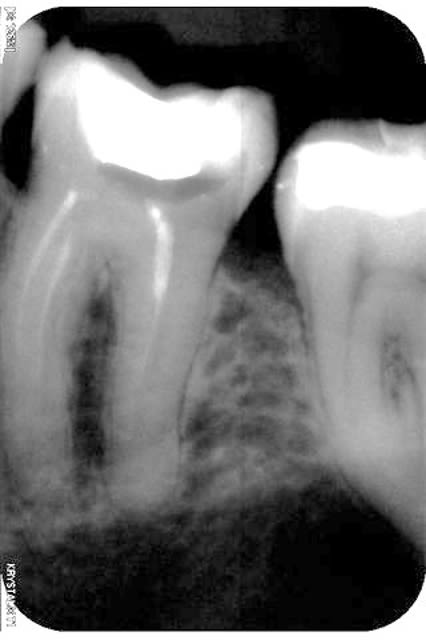

une 46:le pronostic?

35:decouverte fortuite sous un si joli inlay or que je l'ai rescellé(adieu CCC...)

Effectivementm, la 46, pas sur qu'e;;e est le temps de cicatriser. Mais, l'echec sera d'origine paro non endodontique.

un excellent exemple de lesion endo paro. Traitement paro prevu ?

c'est pas un Pb endo qui a fait fiche le camp a l'os. Itiz ze ozer way round, non?

La dent est mobile?

Probleme endo paro ; dans ce cas, le probleme endo doit etre traite en premier.

Le traitement paro en second.